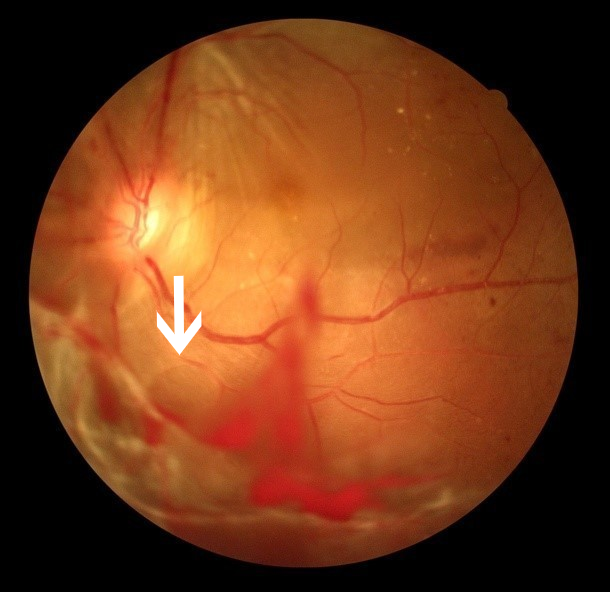

视网膜中央静脉阻塞

眼科ab超检查单怎么看常见眼底疾病检查结果的秒懂解读_https://www.jmylbn.com_新闻资讯_第7张顾名思义,视网膜大血管(静脉)堵了。

眼底彩照:视网膜火焰状出血

图片来源:天津市眼科医院